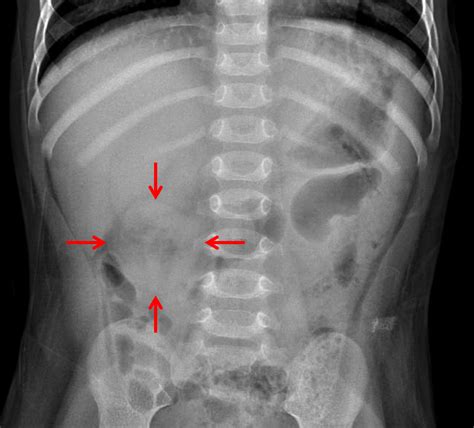

In a healthy individual, gas moves through the bowels alongside digested food and stool, eventually being passed as flatus or absorbed. When a radiologist describes the pattern as "nonobstructive," they are confirming that the gas is scattered in a way that is consistent with normal physiological function, rather than being trapped in a dilated loop that indicates a mechanical blockage.

By identifying a nonobstructive bowel gas pattern, physicians can effectively rule out a mechanical blockage as the primary cause of acute, life-threatening symptoms. This allows the medical team to shift their focus toward other potential causes of discomfort, such as:

Imaging reports can be difficult to translate for the layperson. When you see terms like "nonobstructive," it is a clinical way of saying "this part is normal." The following table summarizes the key differences between a normal gas pattern and a problematic one.